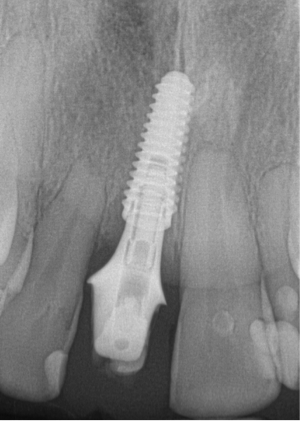

After 4 months of healing and integration of the bone around the implant, the digital workflow was initiated to develop the abutment and treatment plan. Another analog impression was made with an impression post and polyvinyl impression. The laboratory scanned the impression and digitized it to create the emergence profile of the milled titanium abutment and the final restoration (Figure 10 and Figure 11). The patient had a considerably thick soft-tissue profile, allowing a milled titanium abutment. The decision to use a titanium abutment was based on the patient's occlusion and propensity to fracture teeth or restorations. The virtual model was gray because the scanner does not recognize the color of the analog impression. The virtual final abutment and crown were approved and fabrication completed. The final restoration met the patient's esthetic values and his ability to function (Figure 12 and Figure 13).

The young man was evaluated at 2 weeks (Figure 25 and Figure 26) and again at 6 weeks (Figure 27). The remaining natural teeth and the implant were stable. The natural teeth had a reduction in mobility to plus 1 at most. The patient's expectation was met. The soft-tissue element of his smile was maintained, and the patient is considering more cosmetic dentistry to optimize his smile. At 16 weeks postoperatively, the radiograph suggested that the digital workflow provided a great benefit to the patient and reduced the amount of chair time in the dental practice, with help from digital technology and the dental laboratory (Figure 28).

Fig 13. Radiograph 6 months after cementation.

Figure 13

Fig 25. Postoperative periapical radiograph at 2 weeks.

Figure 25

Fig 28. Postoperative radiograph at 16 weeks.

Figure 28